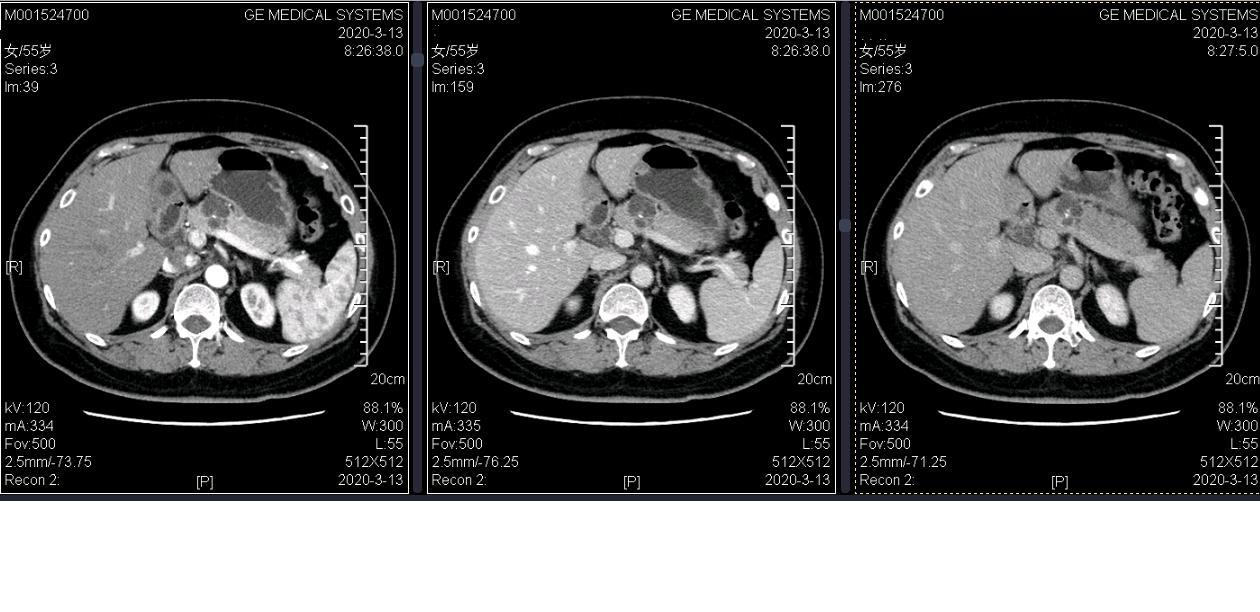

囊性肿瘤是一种以囊性病变为特征的胰腺肿瘤,主要分为浆液性囊腺瘤